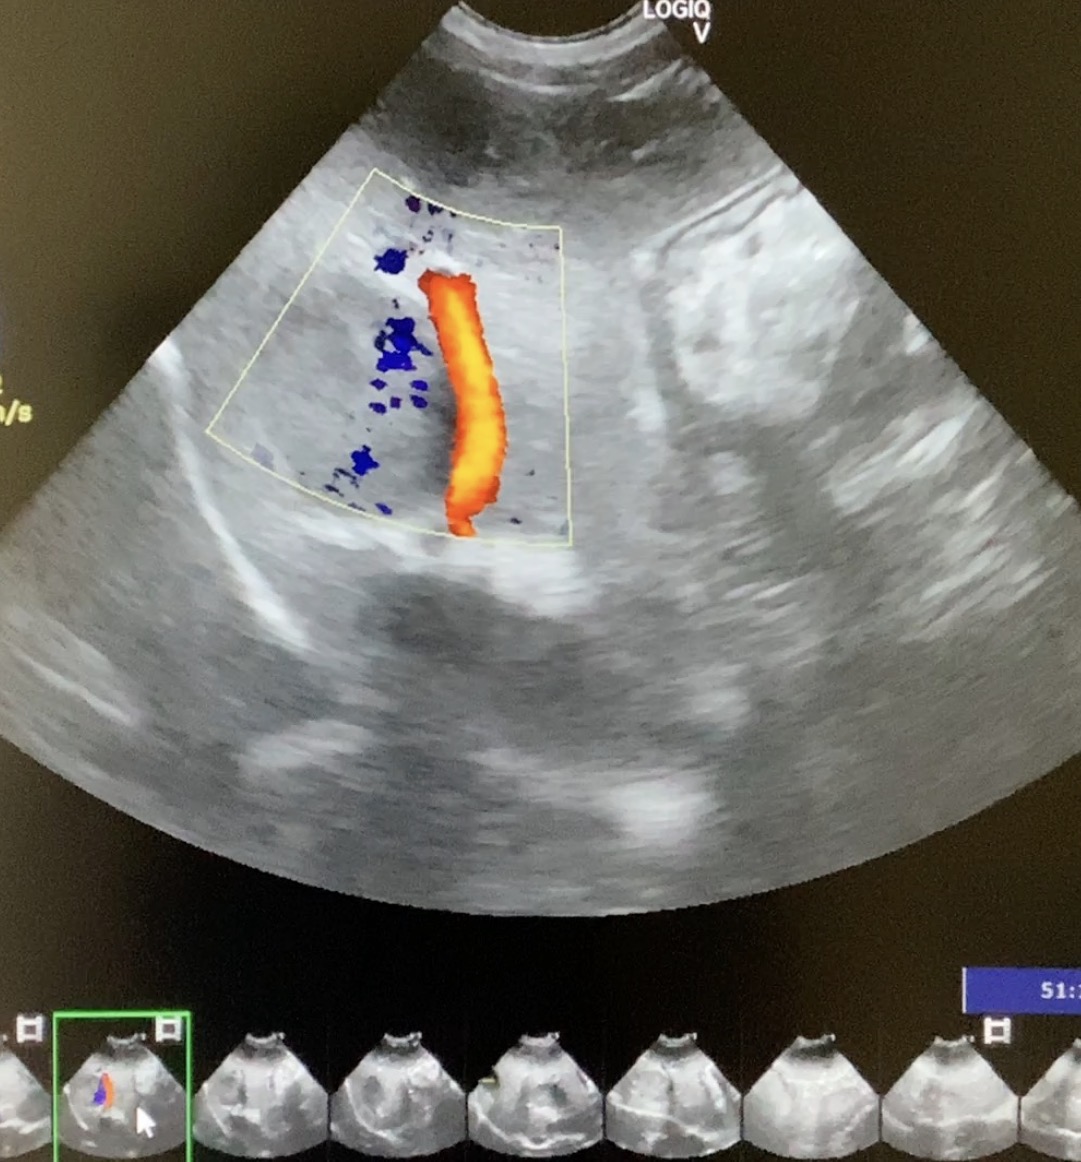

本症例(初診時高齢・小型犬)は、当初、自力での排便が困難となる「会陰ヘルニア」および「直腸憩室(腸の一部がポケット状に広がる状態)」を主訴に来院されました。複数回の手術を経てヘルニアを管理していましたが、のちに激しい嘔吐と食欲不振、極端な肝機能数値の異常(測定不能レベルの上昇)を呈し、超音波検査で肝臓に腫瘤(マス)が発見されました。

This post details our surgical and medical approach to a complex case involving recurrent severe perineal hernia and a malignant liver lymphoma in a senior dog. We emphasize the grim reality of untreated conditions and the severe risks of anesthesia when underlying heart and respiratory diseases are present. To maximize safety, we exclusively use local infiltration anesthesia. Due to a lack of available autologous tissue, a polypropylene mesh and extensive organ pexy (both colon and bladder fixation to the abdominal wall) were required to prevent fatal urethral obstruction and re-herniation. Additionally, simultaneous castration was performed to shrink the enlarged prostate, a key factor in hernia development, thereby reducing the risk of recurrence. For the liver tumor, given its deep location at the liver base and the high risk of fatal bleeding, we opted for a biopsy which confirmed lymphoma. Unfortunately, the patient’s elevated bilirubin and the family’s preference for a compromised, single-agent chemotherapy protocol led to early drug resistance. We candidly discuss the harsh realities of end-stage cancer—it is a painful decline characterized by severe cachexia and organ failure that palliative care can only partially ease. Furthermore, we outline our strict early discharge policy (1-3 days), the physical limitations of our unstaffed overnight remote monitoring, and our referral policy for highly specialized surgeries. We believe in providing honest, logical medical facts rather than false hope, ensuring families can make fully informed and responsible decisions.